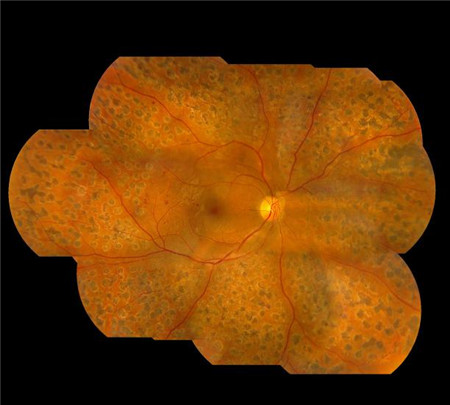

玻璃體視網膜,希瑪瑞視眼科,上海眼科醫院

實際上,視網膜病變并不等于視力下降,這是因為在大多數情況下,視網膜病變初期并不會出現明顯的視力變化。若是等到出現視物模糊、眼底出血等明顯癥狀時,這個時候就已經非常危險了。

要知道,長期的異常血糖狀態會破壞視網膜上的微絲血管,引起視網膜微絲血管病變,而發生視網膜脫落、黃斑水腫以及玻璃體出血這三種形式的視網膜病變。

不過在早期時,視網膜發生病變的位置可能并非位于視網膜中心,對視力的影響不大。而當視力發生明顯下降時,這個時候往往已經到了中晚期,治療的難度也大大增加。所以,人們常說:糖尿病不可怕,怕的是糖尿病引起的并發癥。